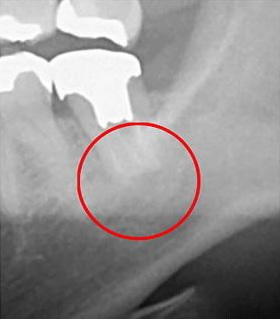

CT撮影を実施することもあります。これも「見える化」の1つです。以下の画像は、CT(3次元)レントゲン(2次元)を使用して同じ患部を撮影した比較画像です。

左側の画像がCTによる撮影で、右側がレントゲンによるものです。

CTで撮影された左の画像では、赤丸で囲んだ部分に黒い影が確認できます。この黒い影は「炎症」を示しています。一方、右のレントゲン画像ではこの黒い影は見えません。これは、レントゲンだけではこのような炎症を見逃してしまうリスクがあることを意味しています。炎症が見逃されると、悪化して最終的には抜歯が必要になる可能性もあります。